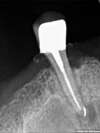

Sauvetage réussi !

Un contrôle régulier du reste de ce kyste se fera les mois suivants.